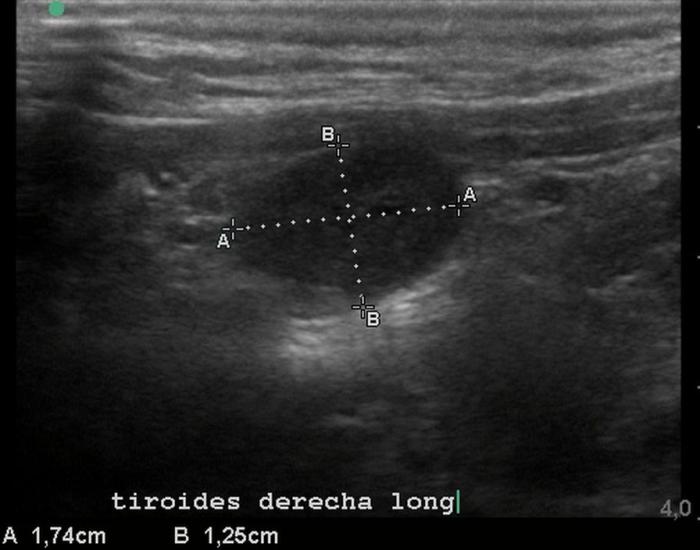

El uso de estructuras vasculares adyacentes como referencias anatómicas ha sido una estrategia útil en ecografía veterinaria para estandarizar las mediciones de órganos pequeños como la glándula tiroides. En este contexto, Bandula Kumara et al. (2019) propusieron la medición de la relación entre el diámetro tiroideo (TD) y el diámetro de la arteria carótida común (CCA) como una forma práctica de evaluar el tamaño de la glándula en perros clínicamente normales (Figura 5A-B).

Los autores realizaron un estudio en el que midieron el diámetro anteroposterior de los lóbulos tiroideos y el diámetro externo de la CCA en cortes transversales obtenidos a nivel del cuello medio. Encontraron que esta relación se mantiene relativamente constante entre razas y tamaños corporales, sugiriendo que puede ser utilizada como parámetro de referencia ecográfica. Específicamente, en perros adultos sanos, la relación TD/CCA fue de 1.74 ± 0.40 (rango 1.11–2.43)6. Si los valores se encuentran por debajo del rango normal pueden ser considerados potencialmente indicativos de hipoplasia tiroidea o atrofia glandular.

Una ventaja de esta relación es que la arteria carótida común es fácilmente identificable ecográficamente, presenta un diámetro estable y poco variable en condiciones fisiológicas, y se ubica en estrecha proximidad con la glándula tiroides. Esto la convierte en una excelente estructura de referencia para normalizar mediciones entre individuos de diferente tamaño corporal, permitiendo evaluaciones objetivas en poblaciones mixtas de perros de compañía.

Además, este índice podría tener aplicación clínica en el seguimiento de animales con enfermedad tiroidea subclínica o en tratamiento, ya que permite detectar cambios discretos en el volumen glandular con buena reproducibilidad interobservador. Aunque su utilidad clínica requiere aún validación en animales con patología confirmada, representa una herramienta complementaria valiosa dentro del enfoque ecográfico sistemático de la glándula tiroides en pequeños animales.